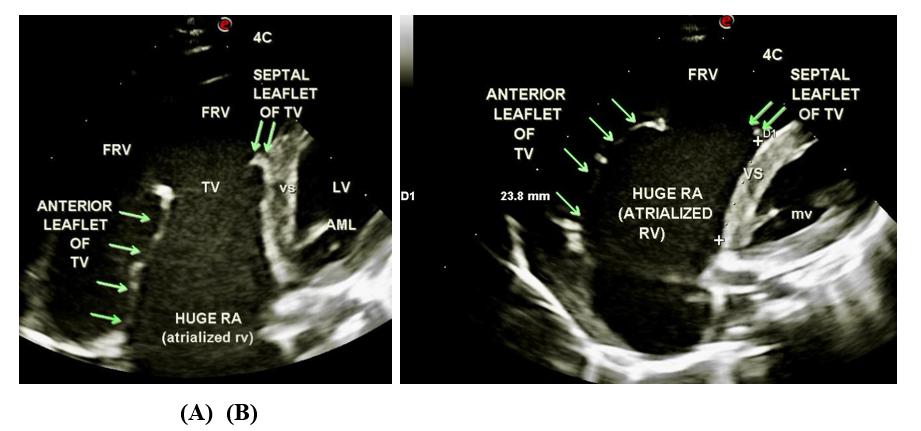

Figure 1: Transthoracic echocardiography. (A) Apical 4C view shows apically displaced small septal leaflet and large, sail like and redundant anterior leaflet of TV. FRV, functional right ventricle; TV, tricuspid valve; AML, anterior mitral leaflet; LV, left ventricle; mv, mitral valve.